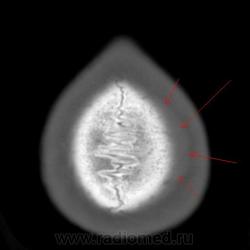

Здравствуйте. Сегодня на дежурстве попросили взять мальчика 13лет, который лежит в гемо по поводу острого лейкоза. Направили посмотреть голову с диагнозов опухолевидное образование темени. Сделал и мягкотканную и костную реконструкцию... Что писать? Немного эрозирована кость. Как описать данную картину грамотно и чему это может соответствовать?

небольшая эрозивность и что-то мягкотканное...

Очагово-деструктивные изменения с образованием опухолевого узла (лейкемическая инфильтрация?). Биопсия. Болезненно ли? Трубчатые кости не имеют подобных изменений?

Напишу как вариант: периостоз с лейкемической инфильтрацией... Заключение сейчас отдавать уже. Трубчатые кости не снимали...